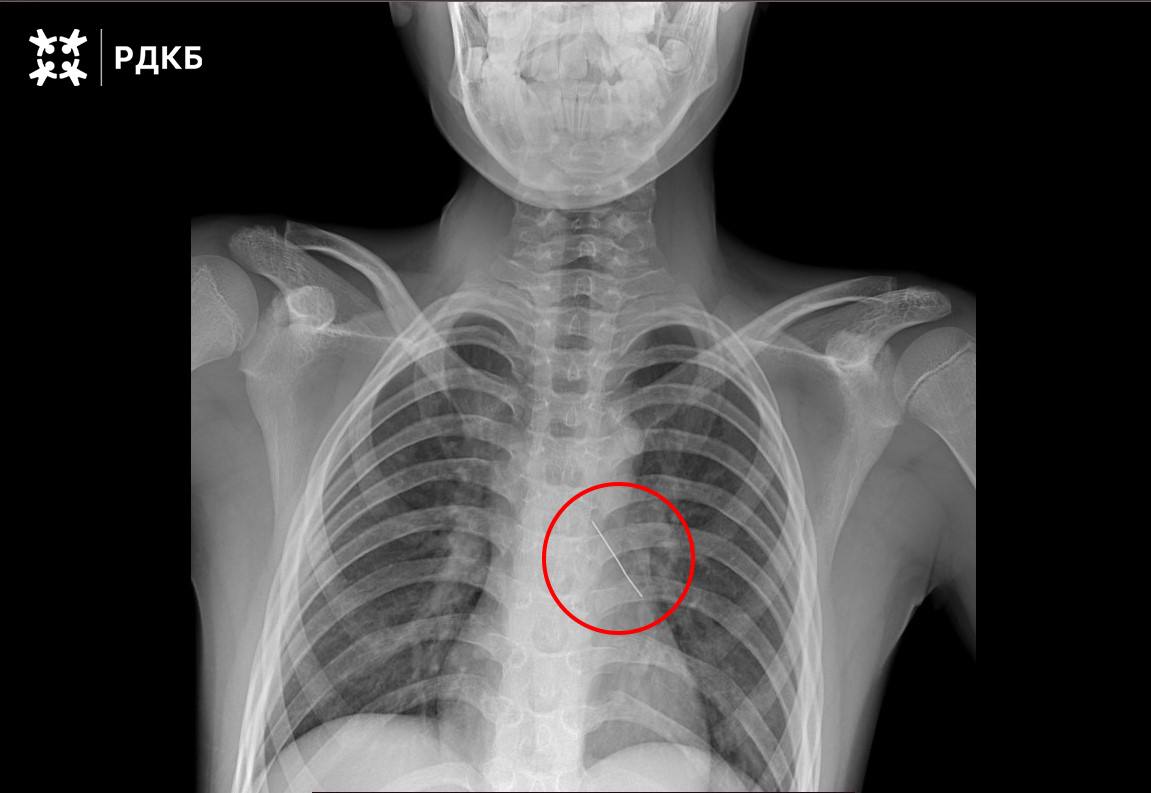

Ребенка, вдохнувшего булавку, спасли московские хирурги.

В Российскую детскую клиническую больницу поступил одиннадцатилетний мальчик, его экстренно доставили бортом санавиации из Калининградской области.

Специалисты аккуратно извлекли булавку с помощью оптических щипцов, и через три дня подростка уже выписали.